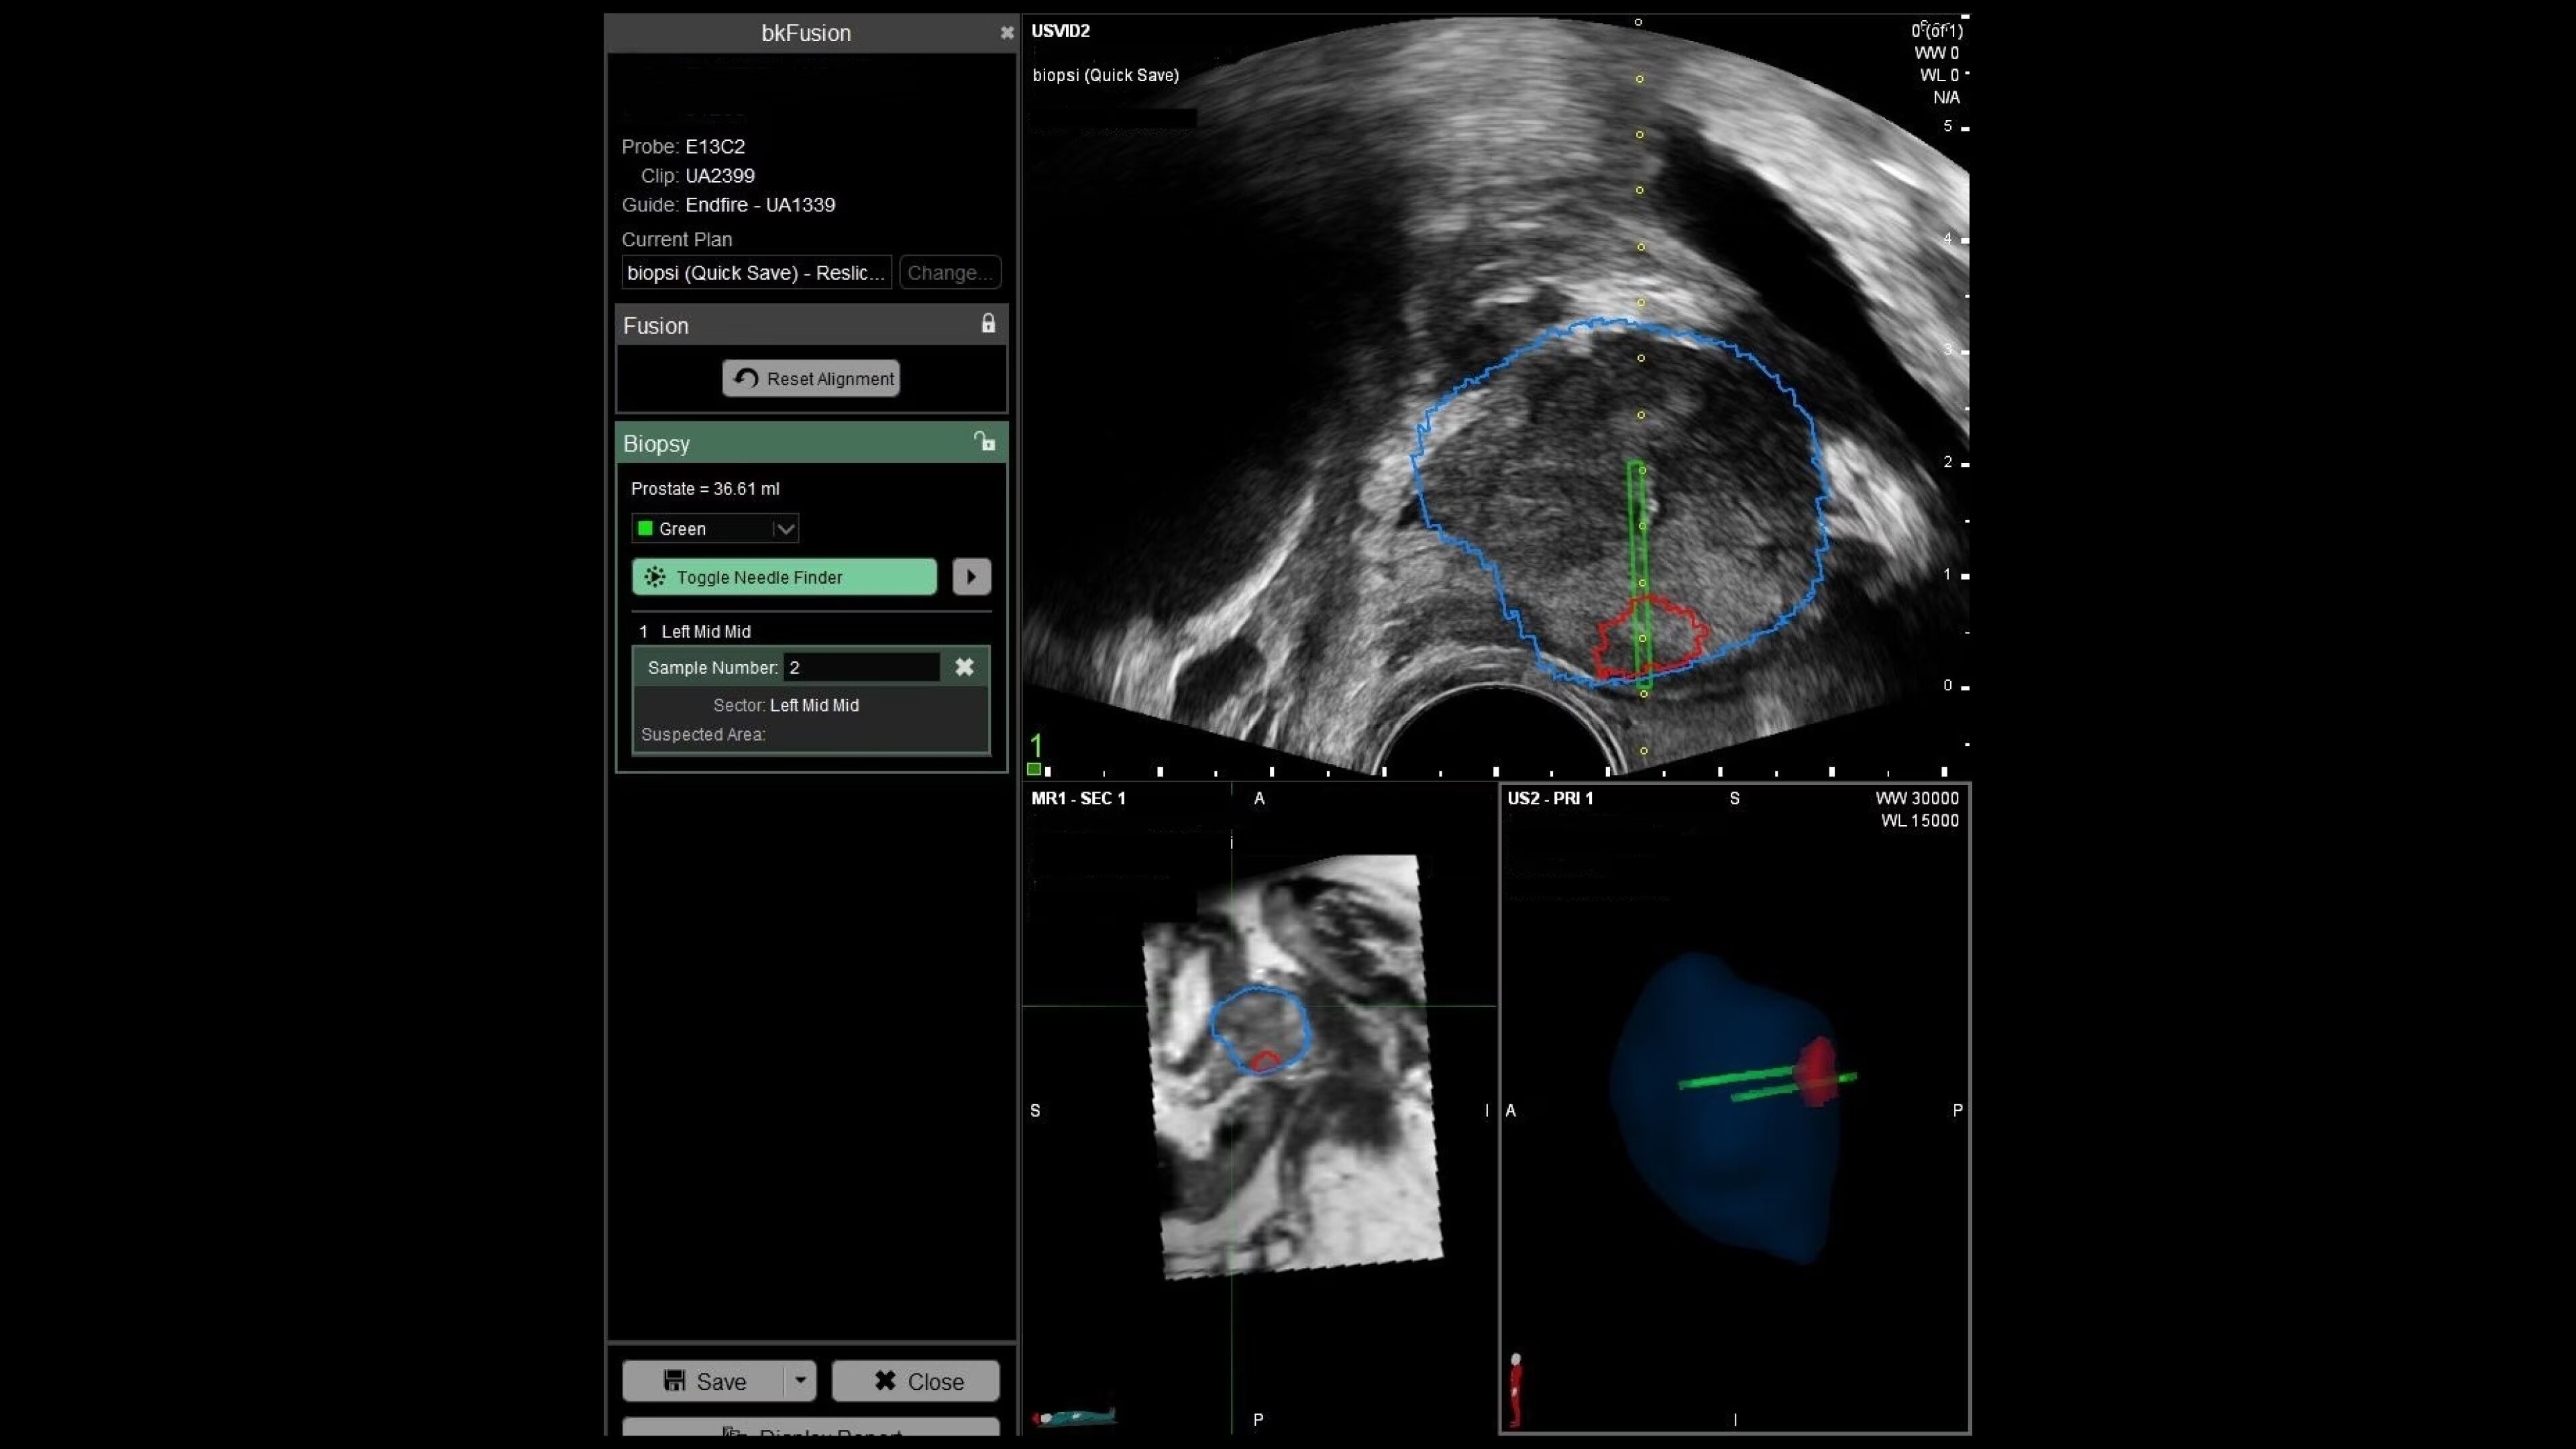

bkFusion–MRI-ultrasound Fusion Biopsy Solution

bkFusion offers advanced MRI-ultrasound fusion for high precision prostate biopsies. Benefit from high spatial resolution, fast workflow, and flexible biopsy options.

bkFusion is a fast, flexible, and effective MRI-ultrasound fusion prostate biopsy solution. Clinically proven to have effective detection rates¹, bkFusion offers a streamlined workflow designed for urologists. It provides the flexibility to choose from a range of options for transperineal and transrectal prostate biopsies. bkFusion is the only MRI-ultrasound fusion solution guaranteed to work with your ultrasound system, powered by unique Predictive Fusion® software for reliable image registration.

With bkFusion, confidently target your biopsy with clear visualization of organ borders to detect registration errors or deformations in real-time. bkFusion, MRI-ultrasound fusion biopsy solution features proprietary imaging algorithms developed with high spatial, temporal, and contrast resolution for advanced visualization.

bkFusion has proven to accurately detect 84% of PIRADS 3-5 lesions and up to 81% GG>=2 cancer.¹

Predictive Fusion® is the proprietary registration method allowing you to imediately see any errors in the overly of MRI and ultrasound images before and during the procedure. Utilizing rigid 2D slice registration, it eliminates distortion in merging 3D shapes, ensuring precise MRI-ultrasound fusion. If changes are needed, make simple, one-touch, micro-adjustments to updte the registration without calibration steps or 3D sweeps. Enhance your prostate biopsy accuracy with this advanced technology.